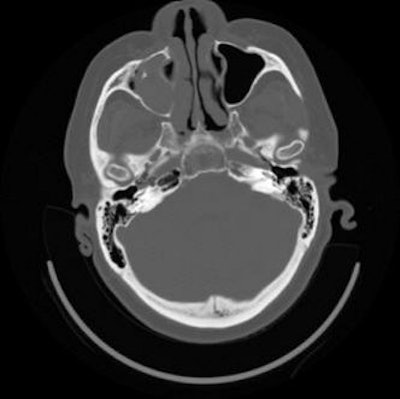

| A right orbital floor fracture that was missed. Ancillary findings should increase suspicion for specific pathology. Blood in a maxillary sinus is a finding on axial images that is highly suspicious for an orbital floor fracture. The fracture itself may be difficult to discern because it is in the plane of imaging. Images courtesy of Dr. Barton Branstetter IV. |